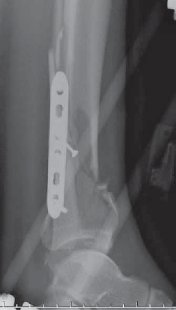

62.

An anterior plate location is often best for neutralization or buttressing of complex intra-articular fractures. TECH FIG 5 • A,B. Lag screws are used and anterior plating is performed to optimize fixation of the articular segment with a raft of anterior–posterior screws. Autograft from the tubercle of Gerdy was used above the disimpacted articular surface, but allograft or substi- A B tutes may be used.

TECH FIG 5

(continued)

• C,D. Radiographs show appearance immediately postopera- C D tively. #### WOUND CLOSURE AND CARE